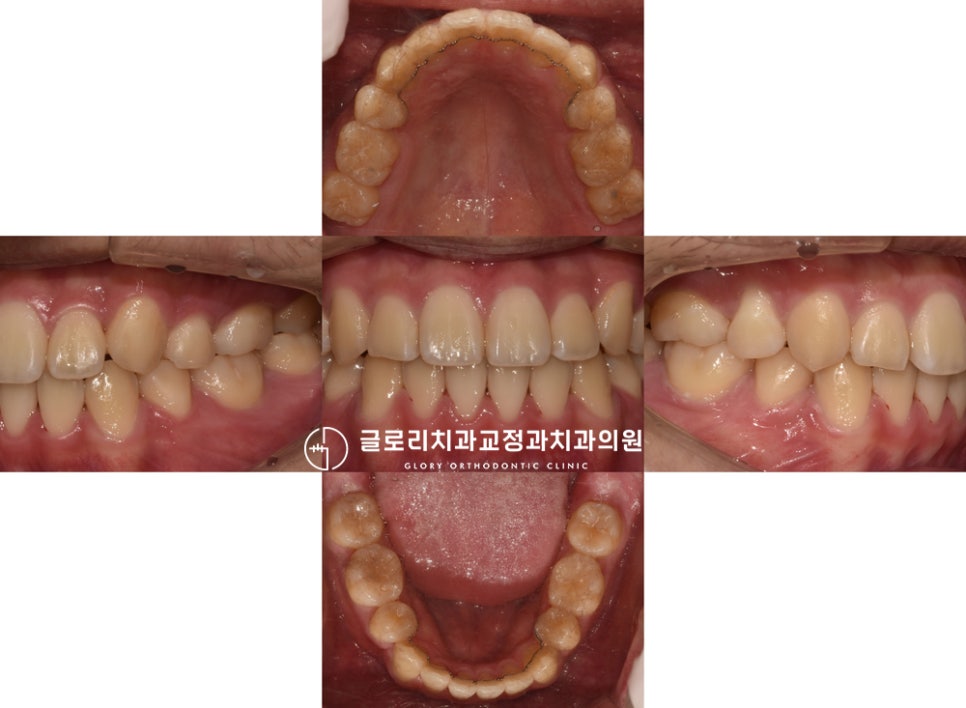

그 결과 아래와 같은 모습으로 바뀌었습니다.

정중선도 알맞게 잘 맞고 있었으며

전체적으로 고르게 바뀐 것을 볼 수 있는데요.

문제가 되었던 치열과 교합이 해결되어

이전에 비해 훨씬 건강하고

안정적인 배열이 되었네요.

무엇보다 음식을 먹는 것에 있어

즐거움을 느끼게 되었다는 환자분,

면 종류 음식도 잘 끊어 먹는다며

스리슬쩍 자랑까지 하셨는데요.